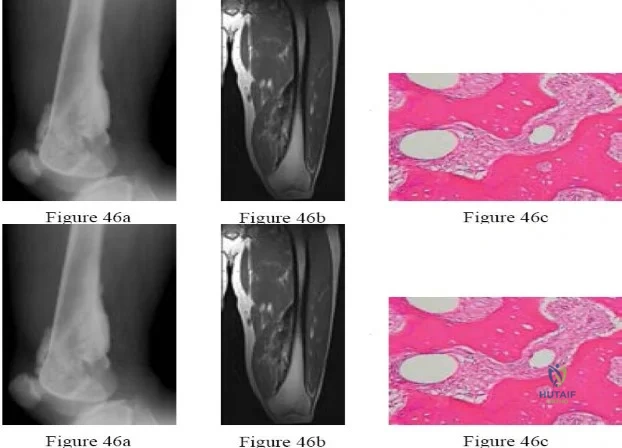

Question 46

During a normal walking gait cycle, what is the primary kinematic function of the hip abductors (gluteus medius and minimus) during the single-leg stance phase?

Explanation